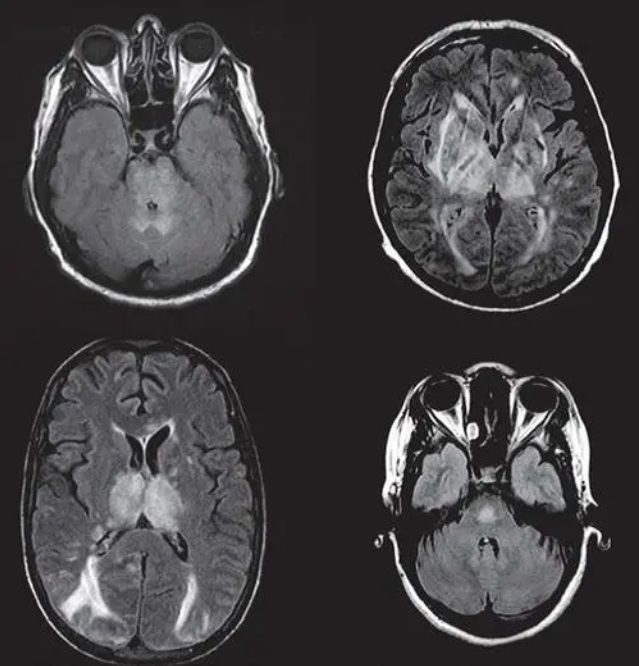

结果:氢气吸入明显提高脓毒症小鼠的7 d存活率(P<0.05)。Y-迷宫实验显示脓毒症时小鼠的自发交替百分比下降,而氢气治疗提高了小鼠的自发交替百分比(P<0.05)。Nissl染色、TUNEL凋亡和投射电镜显示脓毒症时小鼠神经元及海马组织线粒体损伤明显,神经元凋亡增加,氢气治疗减轻神经元和海马组织线粒体损伤,减少细胞凋亡。与Sham组相比,CLP组小鼠海马组织中TNF-α和IL-6升高(P<0.05);与CLP组相比,CLP+H2组小鼠海马组织中TNF-α和IL-6下降(P<0.05)。与Sham组相比,CLP组小鼠海马组织MMP、ATP含量和线粒体呼吸链复合物I活性降低(P<0.05);与CLP组相比,CLP+H2组小鼠海马组织MMP、ATP含量和线粒体呼吸链复合物I活性升高(P<0.05)。各组海马组织中线粒体呼吸链复合物II活性无差异(P>0.05)。与Sham组相比,CLP组小鼠海马组织线粒体生物合成相关蛋白(PGC-1α、NRF2、Tfam)表达增加(P<0.05);与CLP组相比,CLP+H2组小鼠海马组织线粒体生物合成相关蛋白(PGC-1α、NRF2、Tfam)表达进一步增加(P<0.05)。与Sham组相比,CLP组小鼠海马组织Drp1表达增加(P<0.05),Mfn2表达减少(P<0.05);与CLP组相比,CLP+H2组小鼠海马组织Drp1表达减少(P<0.05),Mfn2表达增加(P<0.05)。结论:氢气治疗提高脓毒症小鼠存活率,改善认知功能,减轻脓毒症引起的脑损伤,具有抗凋亡、抗炎作用。氢气对脓毒症相关性脑病的保护作用与其改善线粒体功能,调节线粒体生物合成和线粒体融合/分裂有关。第二部分:氢气激活PGC-1α促进线粒体生物合成减轻脓毒症相关性脑病目的:探讨氢气对脓毒症相关性脑病小鼠海马组织线粒体生物合成的影响及相关机制。